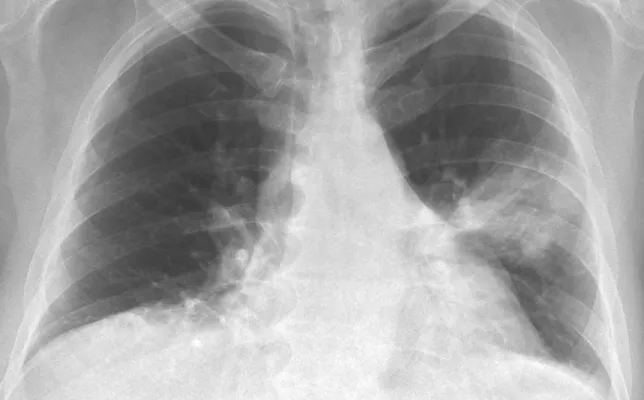

Los casos clínicos presentados corresponden a ejemplos seleccionados de la práctica radiológica, con fines educativos y de actualización profesional. Cada caso incluye hallazgos relevantes, diagnóstico diferencial y comentarios orientados al razonamiento radiológico. Todo el material ha sido anonimizado y se publica respetando los criterios de confidencialidad y privacidad del paciente.